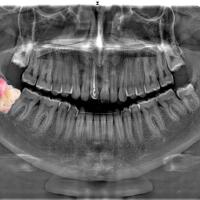

Siendo mi carrera la Odontología mientras la curiosidad y vocación de servicio forman parte de mis motores; enfoqué esta gran problemática a mi área hasta mis posibilidades siendo estudiante y es así como llegué a la posibilidad de participar en un verano de investigación como mis primeros pasos para ser una pieza en el rompecabezas en esta lucha contra el cáncer. El proyecto elegido fue más que ideal: “Expresión proteolítica en quistes y tumores de origen odontogénico” llevada a cabo en la ciudad de León, Guanajuato del 18 de junio al 4 de agosto del año 2023.